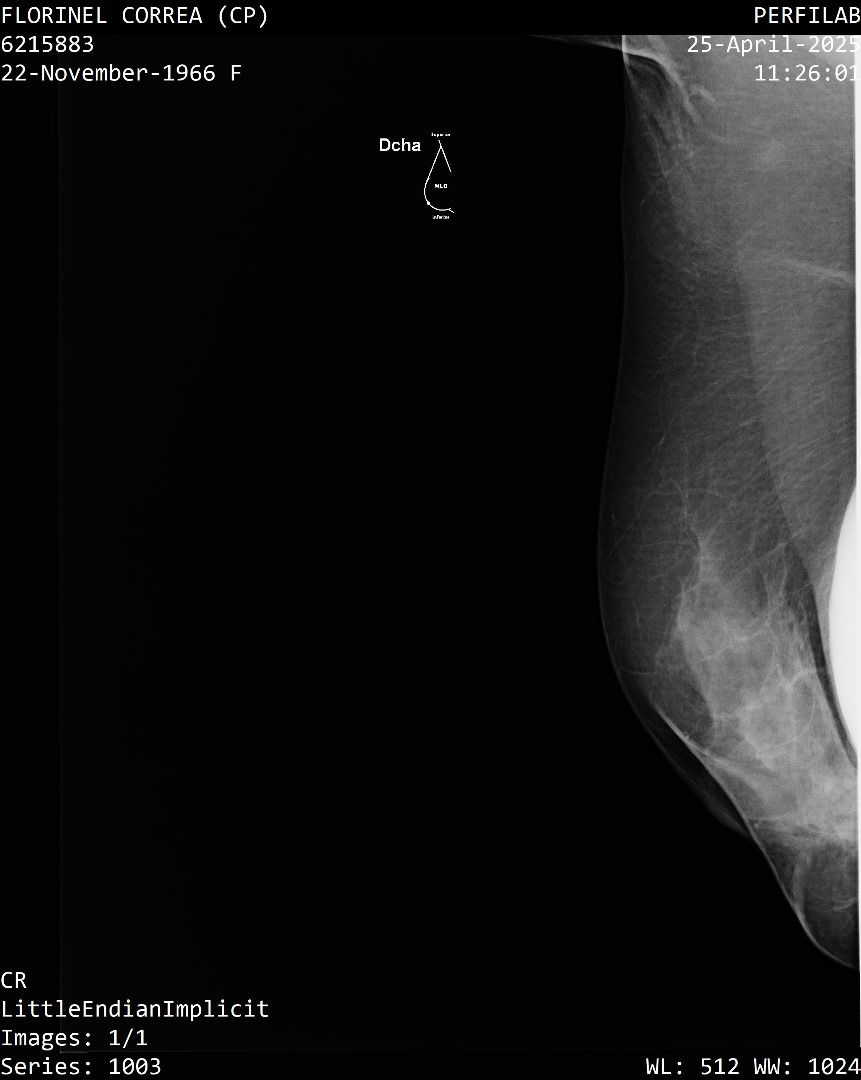

A Correa se le practicó un estudio de mamografía bilateral, la cual reporta una densidad mamaria heterogéneamente densa (ACR C), lo cual puede dificultar la detección de lesiones sospechosas.

Además, la presencia de implantes mamarios limita aún más la visibilidad del tejido mamario.

También se identificó un ganglio linfático de aspecto residual en la axila derecha que se considera sospechoso con este método, requiere evaluación urgente mediante ecografía mamaria.